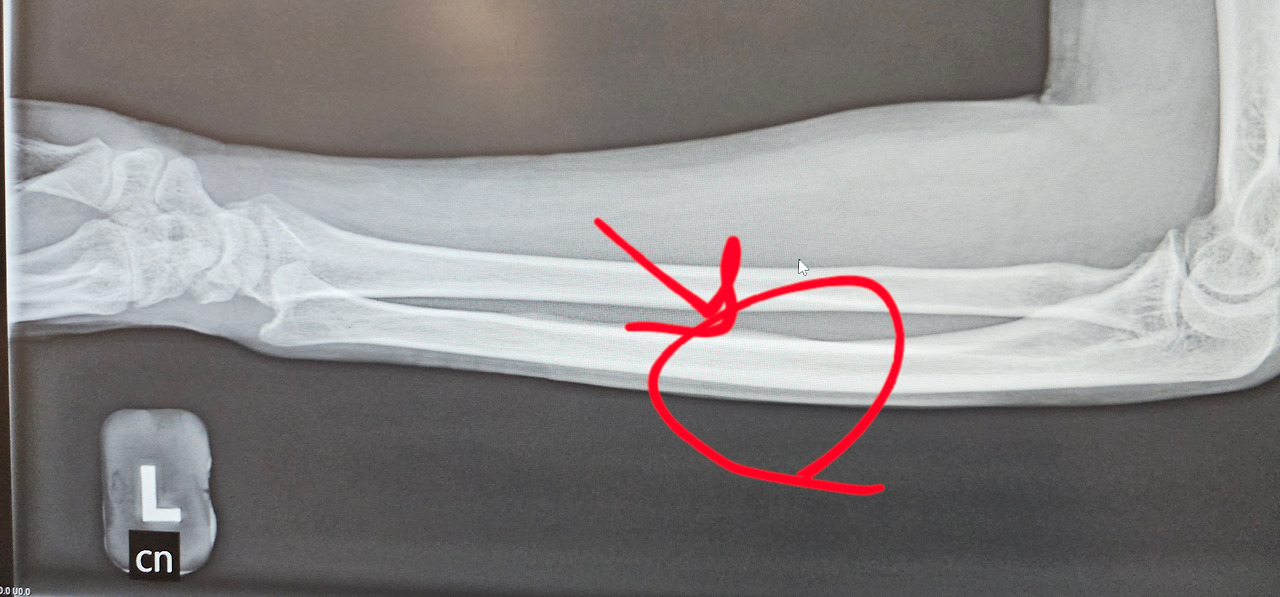

엑스레이를 본 의사는 나에게, 부러진 건 분명히 아닌데 실금이 간 것이니 이제부턴 정말 아무것도 하지 말고 꼼짝하지 않은 채 지내라고 협박 아닌 협박을 했다. 그래서 구입한 팔걸이까지 하고 출근을 하니 회사 동료들 모두 입을 모아 “ 어쨰, 넘어져서 손목에 금이 간걸 만만히 보더라니…쯧쯧.. 한참 가겠어” 라며 한 마디씩 했다.

KakaoTalk_20260415_174704371_04.jpg

KakaoTalk_20260415_174704371_03 (1).jpg 실금간 뼈 마디...꼼짝못하는 갑옷을 착용하고 나서야 낫기 시작했다.